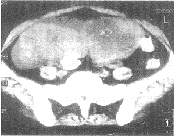

图3 透明细胞癌 CT平扫示左侧卵巢不规则形实性肿块,大小为7.0cm×6.0cm×5.5cm,伴有大量腹水 图4 腺癌 CT平扫示右侧卵巢不规则形囊性肿块,囊壁厚薄不均